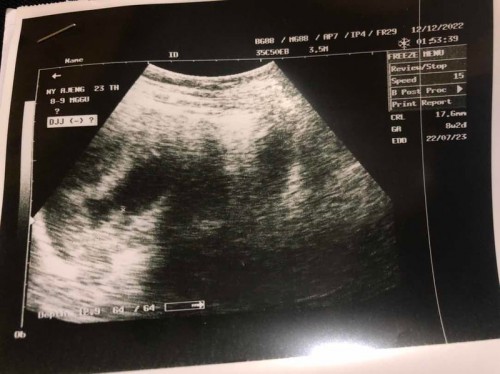

Hasil usg janin tidak berkembang

Wktu itu saya usg usia janin 7week Setelah sebulan kemudian usia janin 8week (hanya bertambah 1 week aja) hpl pun berubah 1bln lebih lambat. Tp saya ga merasa gejala2 nya selama hamil pun blm prnh ada keluhan apa2, flek maupun pendarahan selama hamil jg blm pernah. Dokter bilang janin tidak berkembang. Kalo kaya gini apa masih bisa diselamatkan?🥹😭 mohon pencerahannya😭

saya perdana banget USG. sya tidak paham dan tak pengerti krna dokternya rusuh gk ngejelasin apapun. saya menikah sudah 7 th. tnggl 29 nov kmrn. sya sedang ovulasi. sya cek ke bidan katanya mudh²n ini lagi terjadi pembuahan. lalu sya di kasih vitamin. daan pulanh dr situ smpai hari ini sya merasa payudara kencang, kram prut ringan, sesekali sakit pinggang. perut kembung sering kentut. jntung berdebar². dari artikel yg sy baca katanya tanda² pembuahan berhasil (hamil) itu seperti itu. (maafkan kalau salah bun saya blm pernah hamil) tp pas USG td hasil nya ssperti di gambar. itu pun usg nya hanya sebentar. di deket pusar sebelah kiri. sgkn sya kram sebelah kanan